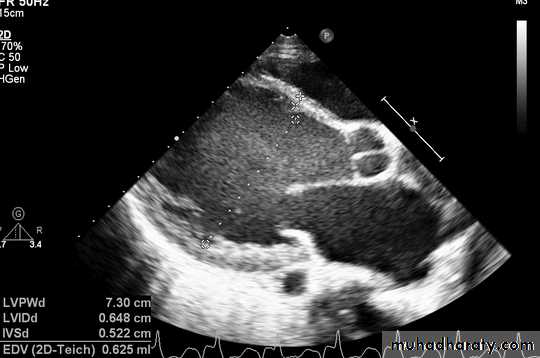

Echocardiogram: Chamber enlargement and global hypokinesis

ECHO

Cardiovascular Diseases